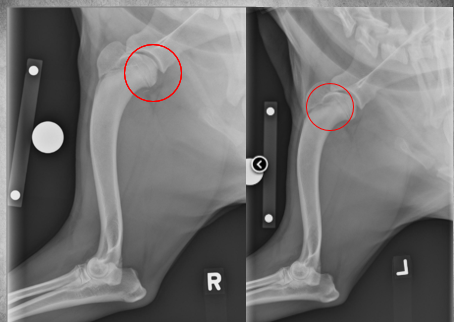

5 months old female Bernese Mountain dog

Played ball with other dogs the previous day

Weight-bearing lameness of left pelvic limb

Mild widening of the left tibial apophyseal physis and small fragment visible at distal portion ->

tibial crest avulsion fracture of growth plate in 5m large breed dog

analgesia and hope it heals okay